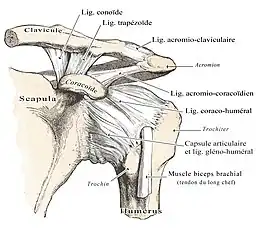

A : ligament acromio-claviculaire. B : acromion. C : ligament coraco-acromial. D : ligament coraco-huméral. E : tendon du long chef du biceps. F : tubercule mineur de l'humérus, ou trochin. G : capsule ligamentaire. H : processus coracoïde. I : ligament coraco-claviculaire (comportant le trapézoïde et conoïde). J : clavicule. K : tubercule majeur, ou trochiter

Le complexe articulaire de l'épaule met en relation quatre os :

- le manubrium sternal (ainsi que le premier cartilage costal) ;

- la clavicule ;

- l'omoplate (scapula) ;

- la tête humérale.

Articulation acromio-claviculaire

Également appelée « articulation cléido-scapulaire », l'acromio-claviculaire est une arthrodie. Elle ne possède donc aucun axe de rotation bien qu'un faible degré de mouvement existe. C'est une vraie articulation puisqu'elle possède une capsule articulaire, une synoviale et deux surfaces articulaires : celle de l'acromion et celle de l'extrémité latérale de la clavicule. Entre les deux surfaces articulaires, on retrouve un fibro-cartilage de type méniscal.

Cette articulation est stabilisée par quatre ligaments, de dehors vers dedans :

- Le ligament acromio-claviculaire qui relie les faces supérieures de l'acromion et de la clavicule ;

- Le ligament conoïde, tendu du processus coracoïde au tubercule conoïde de la clavicule ;

- Le ligament trapézoïde, tendu du processus coracoïde à la ligne trapézoïde de la clavicule ;

- Le ligament coraco-claviculaire médial, de moindre importance.

La capsule articulaire est un manchon fibreux très lâche. Son insertion se fait sur le col de l’humérus et sur la cavité glénoïdale ; elle est renforcée par deux ligaments : un passif et un actif.

Le passif : c’est en fait une individualisation de la capsule articulaire (fragment supérieur), il est constitué de deux ligaments :

- Coracohuméral → deux faisceaux partant du processus coracoïde vers les tubercules majeur (trochiter) et mineur (trochin).